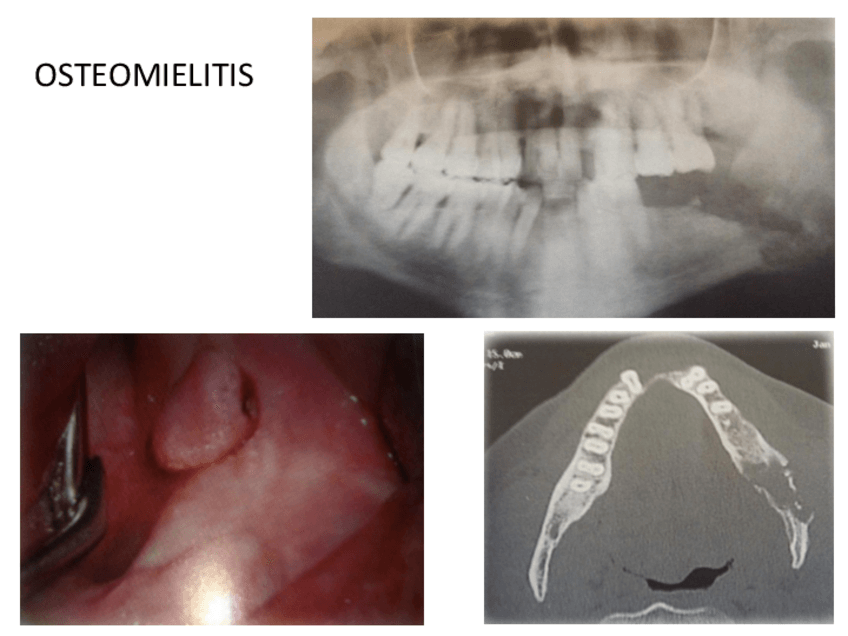

He publicado nuevos apuntes de 3º Medicina Bucal II: Tema-1-INFECCIONES-DE-LOS-MAXILARES-OSTEORADIONECROSIS-Y-OSTEONECROSIS-INDUCIDAS-POR-FARMACOS.pdf

9 páginas